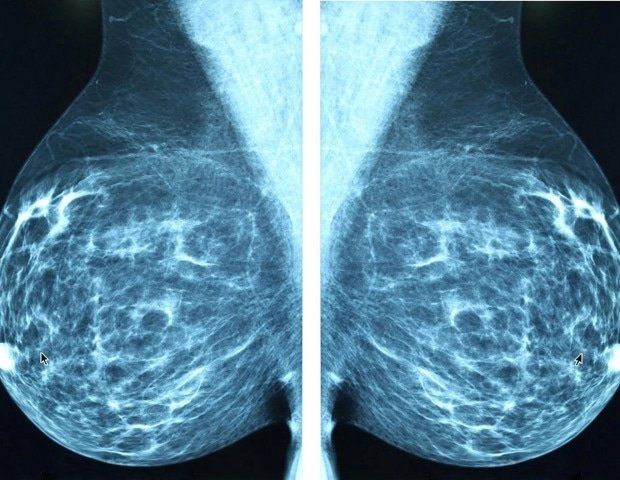

Working with his doctoral student Olya Rezaeian and assistant professor Alparslan Emrah Bayrak at Lehigh University, Asan conducted a study with 28 oncologists and radiologists who used AI to analyze breast cancer images. Clinicians were also given varying levels of explanation for their AI tool ratings. At the end, participants answered a series of questions designed to measure their confidence in the AI-generated assessment and how difficult the task was.